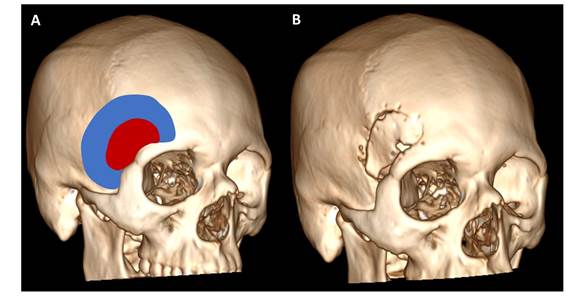

La cirugía realizada fue una craneotomía supraorbitaria lateral más “clipaje” de aneurisma con angiografía con fluoresceína intraoperatoria (Figura 2).

Figura 2 A: Reconstrucción 3D del cráneo del paciente; de color azul una craneotomía pterional, de color rojo una craneotomía supraorbitaria lateral. B: Reconstrucción ósea post quirúrgica del paciente.